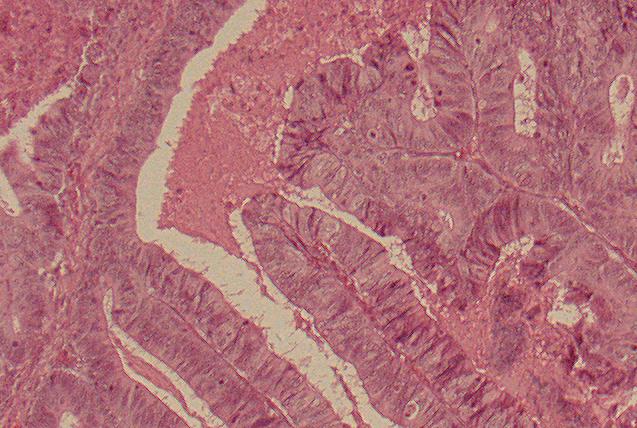

- Formen :

A) 95 % Adenokarzinome (siehe Bilder)